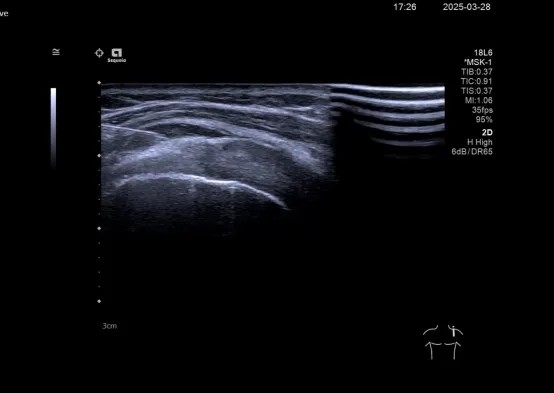

(图为超声引导下肩峰下滑囊增生疗法注射)

(图为康复医学科医生进行超声引导下肩关节增生疗法注射)